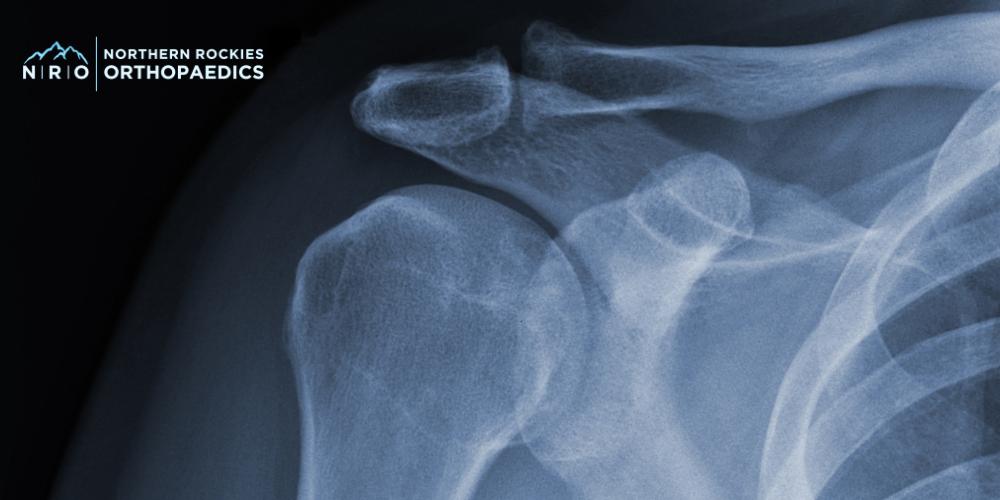

Your visit begins with a comprehensive evaluation by a shoulder specialist who is trained to identify a wide range of shoulder conditions. This includes a discussion of your symptoms, a review of your medical history, and a physical examination to assess the strength, flexibility, and range of motion of your joints. Imaging techniques such as X-rays or MRIs may also be ordered to examine bones, tendons, and soft tissues closely. This thorough process helps us identify the source of your pain and determine the most suitable treatment options for you.